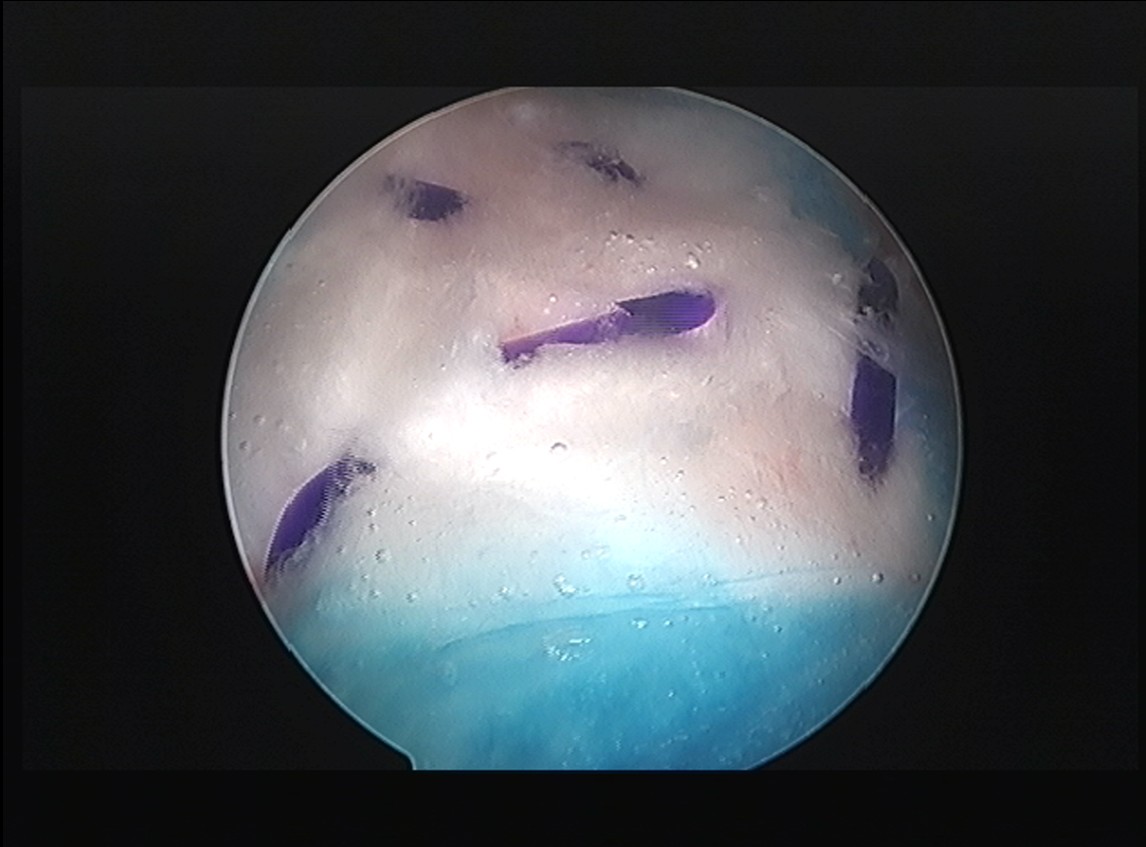

Step 4: 패치 부착

손상된 인대 위에 리제네텐 패치를 부착합니다.

초음파 유도 하에 정확한 위치에 부착

특수 앵커 또는 봉합사로 고정

패치가 인대 표면에 밀착

Step 5: 고정 확인 및 마무리

패치가 제대로 부착되었는지 확인하고 마무리합니다.

초음파로 패치 위치 확인